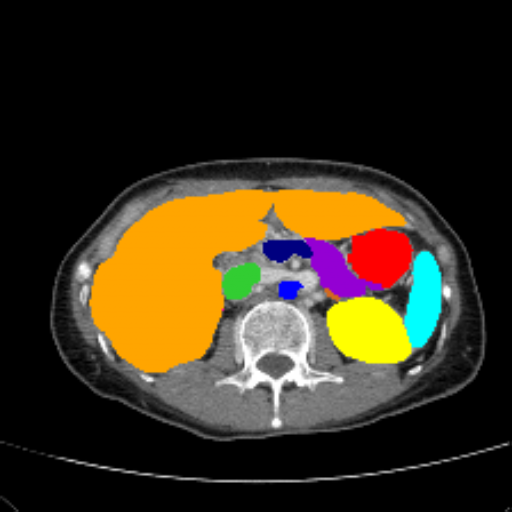

Figure 3 presents a qualitative comparison of segmentation performance on examples from the Synapse, BTCV, ACDC, and ISIC17 datasets. The first two examples (from Synapse) highlight variations in segmentation performance among U-Net, TransUnet, Mamba-Unet, and Swin-Unet. While Swin-Unet performs well in the first example, its performance decreases in the second example, particularly in segmenting the organ highlighted in blue. Additionally, it misclassifies background regions as the class highlighted in orange. In contrast, our approach demonstrates high robustness in segmenting all classes accurately and aligning well with the ground truth masks.

Across BTCV, ACDC, and ISIC17, the comparison methods exhibit varying performance depending on the task and class. For instance, Mamba-Unet struggles to segment multiple organs in BTCV, even misclassifying certain classes as others. In the ACDC dataset, both TransUnet and Mamba-Unet perform poorly in segmenting the three classes. In the last column (ISIC17), Swin-Unet oversegments the skin lesion compared to the ground truth. Unlike the comparison models, our approach consistently delivers effective segmentation across different tasks and datasets.

Refer to caption Refer to caption Refer to caption Refer to caption Refer to caption Refer to caption Refer to caption

Slice GT Unet TransUnet Mamba-Unet Swin-UMamba MambaCAFU-V1

Figure 3: Visual comparison of segmentation examples from Synapse (first two examples), BTCV (3-4 examples), ACDC (5th example) and ISIC17 (last example). Columns: input slice, ground truth, Unet, TransUnet, Mamba-Unet, Swin-UMamba, and MambaCAFU-V1.